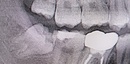

Before(下親知らずの抜歯前) 横に生えた状態で埋まっている親知らず 虫歯がある親知らず 抜歯前の骨の状態のレントゲン像

After(下親知らずの抜歯後) 横に生えた状態で埋まっている親知らずの抜歯後 虫歯がある親知らずの抜歯後 抜歯後の骨の状態のレントゲン像

原因をより詳しく調べるためレントゲンを撮影したところ、右下の親知らずは骨の中に埋まった状態のまま真横に生えて隣接する歯を押しており、前方の歯が虫歯になっています。 そのため、右下の親知らずと隣の奥歯の間には、歯と歯ぐきの境目の溝である「歯周ポケット」が通常よりもかなり深くなっていました。

まず、親知らずと骨の中にある神経の位置、歯や周囲の骨の詳細な情報を確認するために、歯科用パノラマデジタル写真で口腔内を撮影します。撮影結果を踏まえ、抜歯方法や施術の難易度をしっかり確認しました。

1年後、取り除いた親知らず周囲の骨がしっかり再生したことを確認しました。